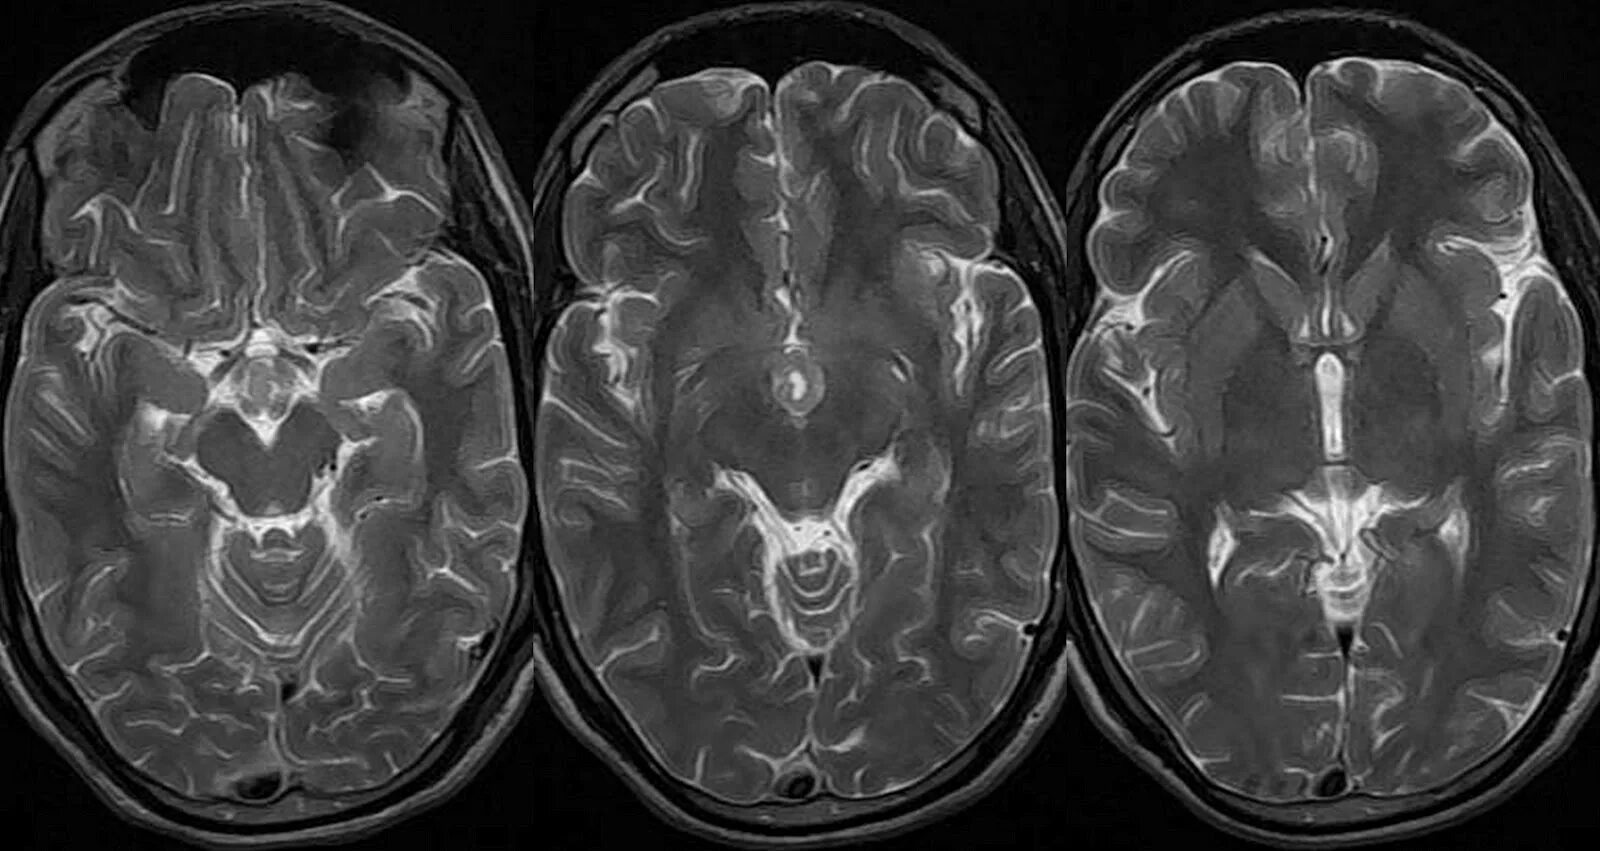

Сколько живут с доброкачественной опухолью головного мозга